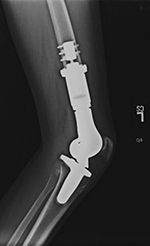

15 year-old girl with history of osteosarcoma of left femur status post resection and prosthesis. Lateral (A) and AP (B) radiographs of the left knee show a distal femur limb sparing prosthesis and knee arthroplasty. |

| 15 year-old girl with history of osteosarcoma of left femur status post resection and prosthesis. Lateral (A) and AP (B) radiographs of the left knee show a distal femur limb sparing prosthesis and knee arthroplasty. |

15 year-old girl with history of osteosarcoma of left femur status post resection and prosthesis. Tc99m whole body bone anterior (C) and posterior (D) projections at different window settings demonstrate mild diffuse increased radiotracer activity around the distal end of the femur prosthesis and proximal end of tibial prosthesis, representing reparative bony remodeling. This can last for many years and is not pathological unless patient complains of new pain in which case one should consider loosening, infection, or recurrence of tumor. |